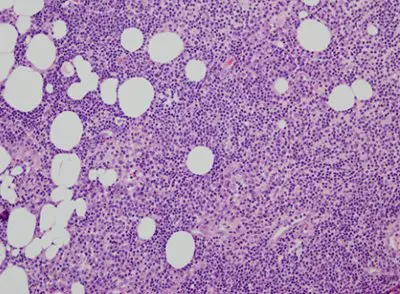

La lesión cutánea fue biopsiada. La biopsia reveló un denso infiltrado perivascular y perianexal compuesto de neutrófilos, linfocitos pequeños e histiocitos en toda la dermis, alcanzando la grasa subcutánea (Figura 1) con tejido de granulación y abscesos subcutáneos. Además se observaron agregados de linfocitos pequeños con contornos irregulares de cromatina nuclear y agrupada, infiltrando las lesiones de hidrosadenitis supurativa. (Figura 2).

Figura 2: Linfocitos infiltrando hidrosadenitis supurativa